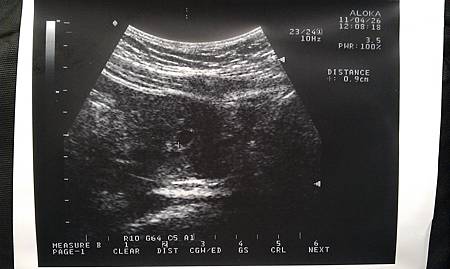

一開始還照不出來,提心吊膽的等啊等,終於等到醫生說可以的那天

就是這一小坨 5W

大約0.9cm 就讓我開始天天有噁心感覺的傢伙

照到了!